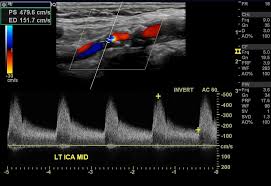

경동맥 초음파 검사는 고주파 초음파를 사용하여 목의 경동맥 혈관을 영상으로 확인하는 검사입니다. 혈관 내벽 두께, 혈류 흐름, 좁아진 정도 등을 실시간으로 볼 수 있으며, 조영제나 방사선 노출이 없어 안전합니다. 검사 시간은 약 20~30분 정도 소요됩니다.

경동맥의 협착 정도와 혈류 속도를 확인해 향후 뇌졸중 발생 가능성을 예측할 수 있습니다.

혈관 내막 두께, 협착 정도, 혈류 속도 등을 확인할 수 있으며, 결과에 따라 추가 정밀검사가 필요할 수 있습니다.